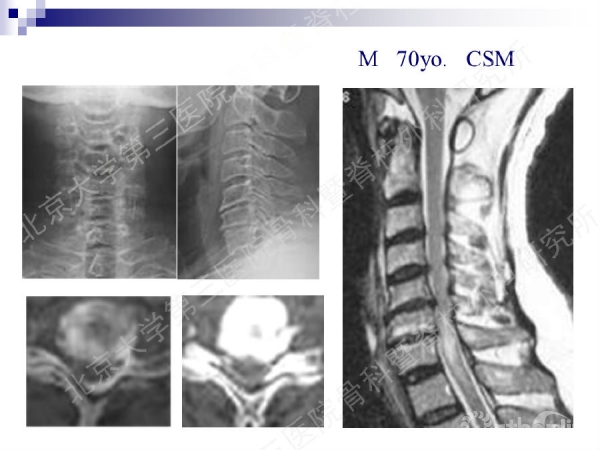

今天,在北京大学第三医院骨科暨脊柱外科研究所刘忠军教授分享的《颈椎人工椎间盘置换手术注意问题》课件中,他将通过大量影像资料、临床研究数据和长期随访结果,给大家介绍现阶段最重要的颈椎非融合技术——人工椎间盘置换术的适应证、禁忌证和其他需要密切注意的一些问题,提醒同道关注与手术技术及内植物相关的尺寸、终板顺列、中心轴线顺列等问题,严格把控手术指征,规范、精准地开展颈椎人工椎间盘置换手术,保障手术疗效。